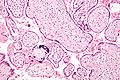

Micrograph of a placental infection (CMV placentitis).